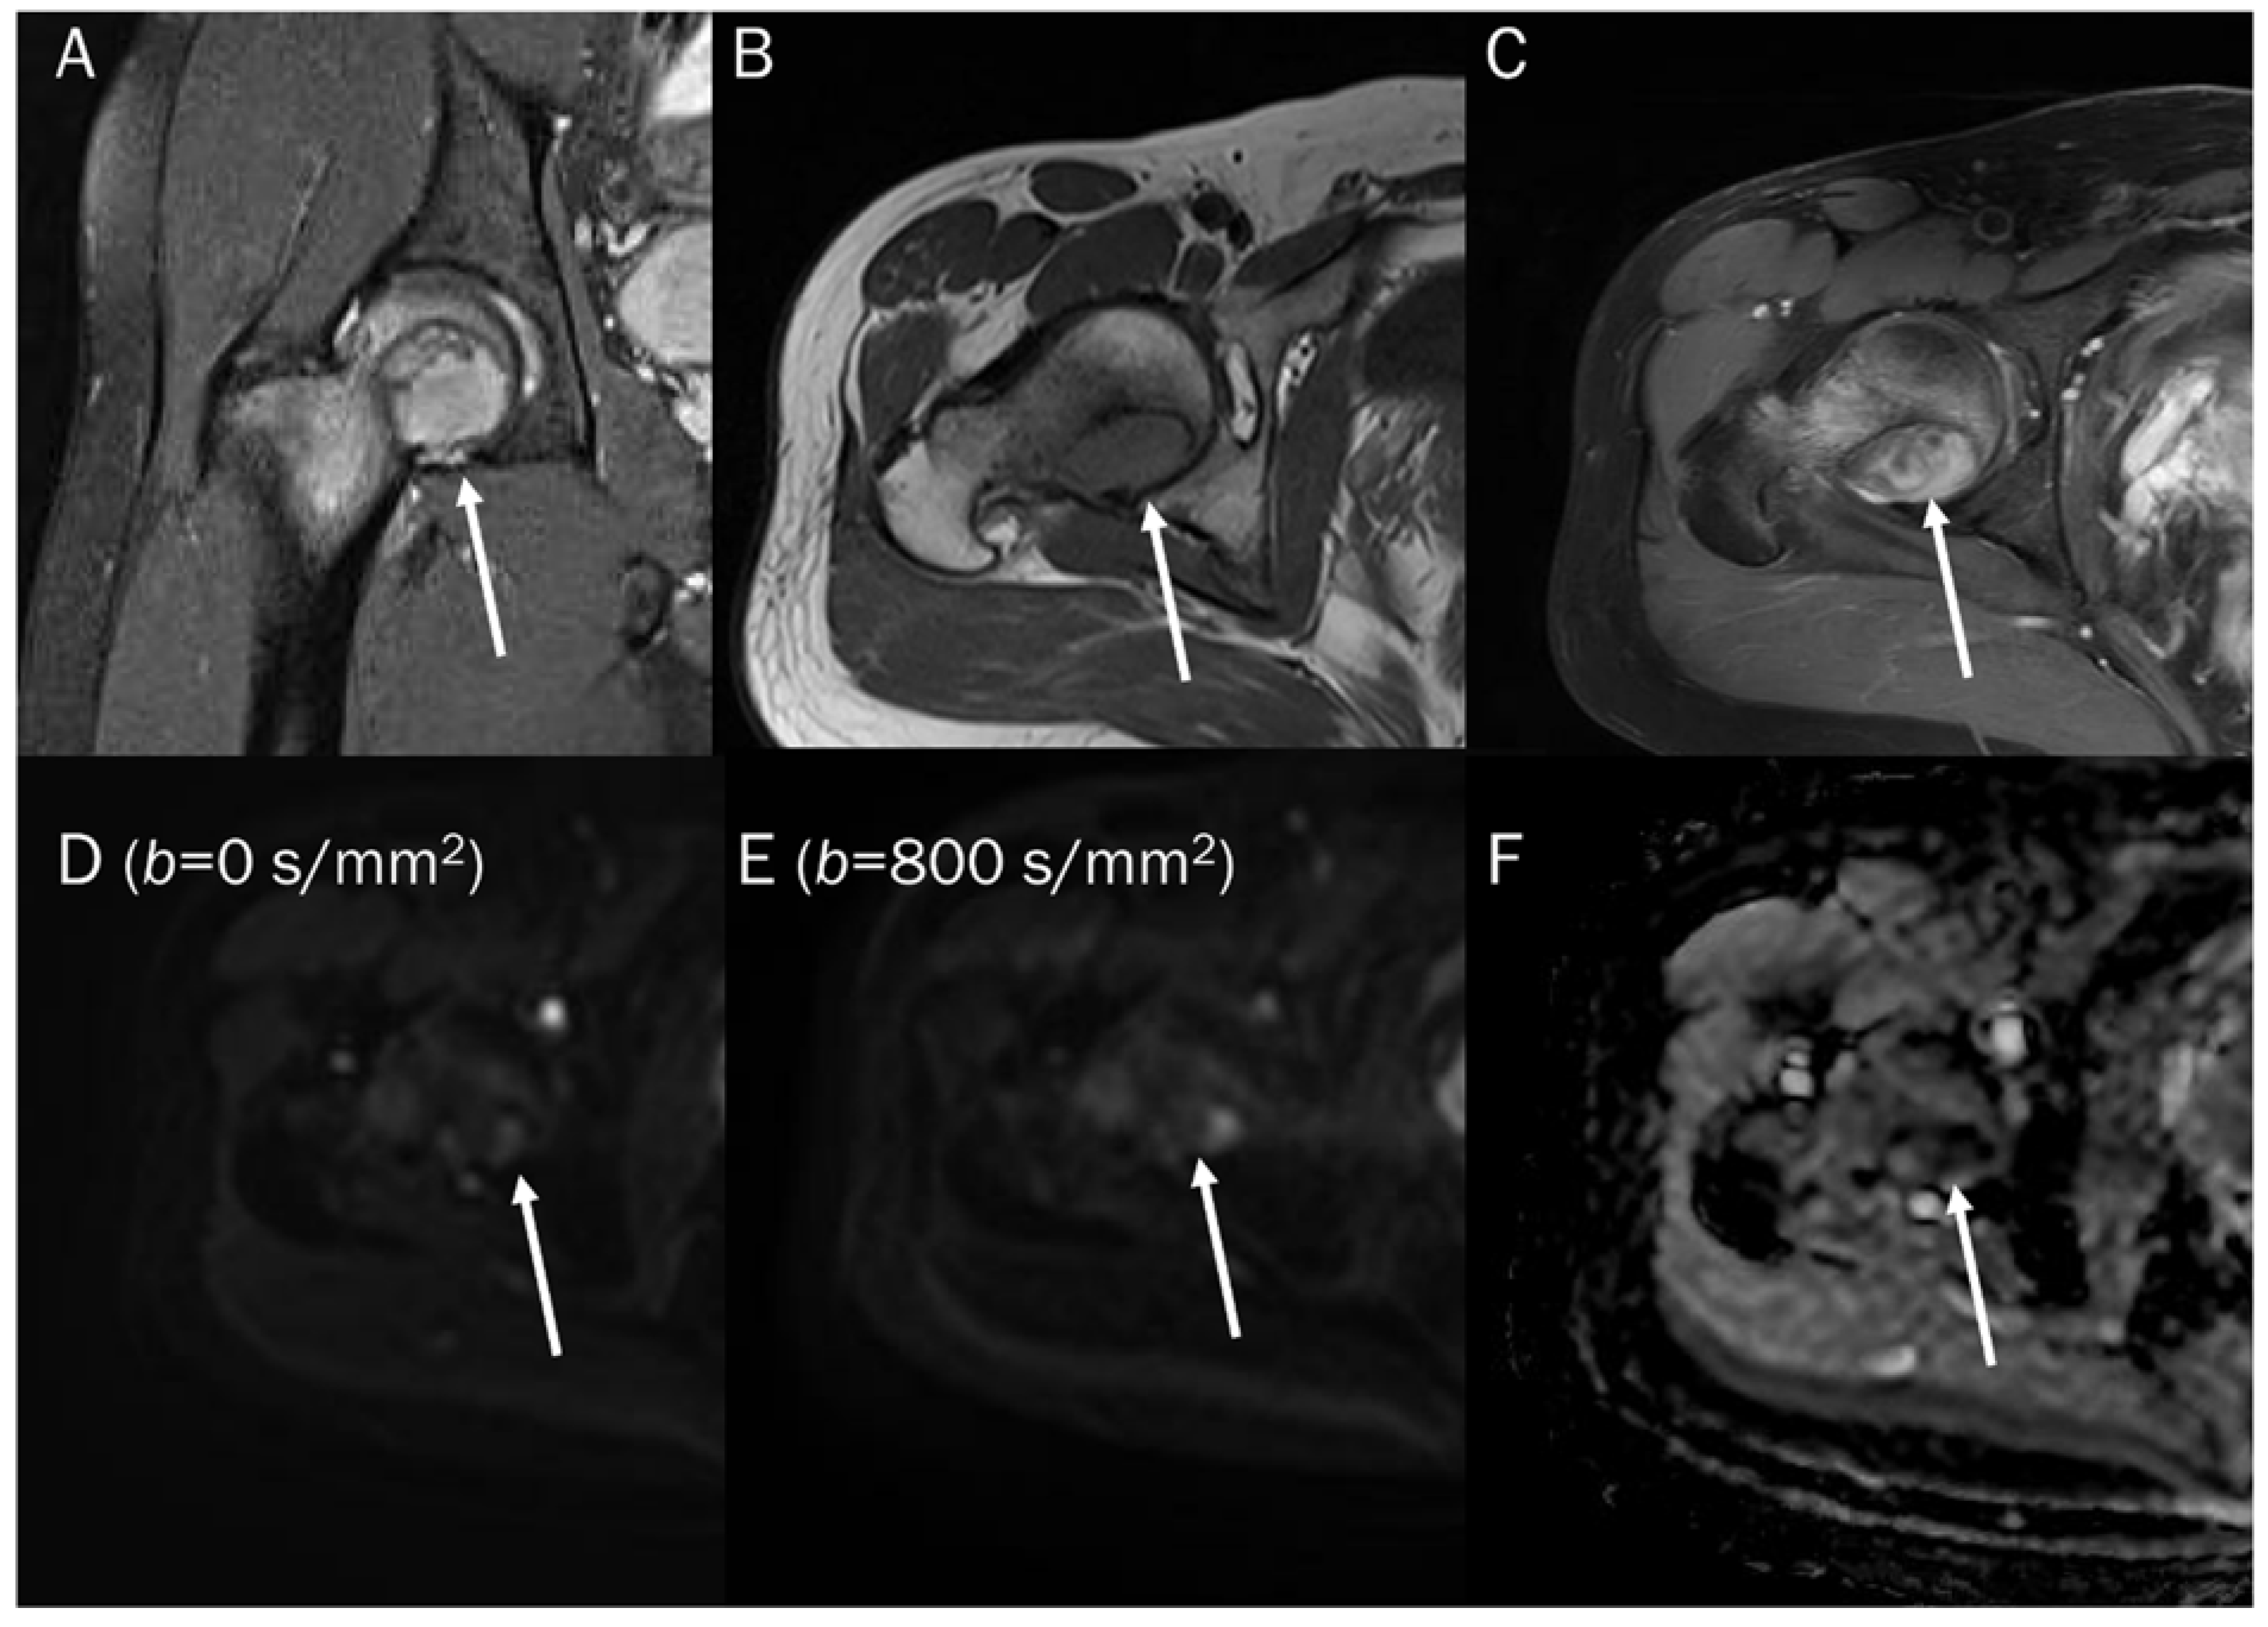

7.3. Benign Bone and Soft Tissue Tumors

- Oka, K.; Yakushiji, T.; Sato, H.; Yorimitsu, S.; Hayashida, Y.; Yamashita, Y.; Mizuta, H. Ability of diffusion-weighted imaging for the differential diagnosis between chronic expanding hematomas and malignant soft tissue tumors. J. Magn. Reson. Imaging 2008, 28, 1195–1200. [Google Scholar] [CrossRef] [PubMed]

- Chhabra, A.; Ashikyan, O.; Slepicka, C.; Dettori, N.; Hwang, H.; Callan, A.; Sharma, R.R.; Xi, Y. Conventional MR and diffusion-weighted imaging of musculoskeletal soft tissue malignancy: Correlation with histologic grading. Eur. Radiol. 2019, 29, 4485–4494. [Google Scholar] [CrossRef] [PubMed]